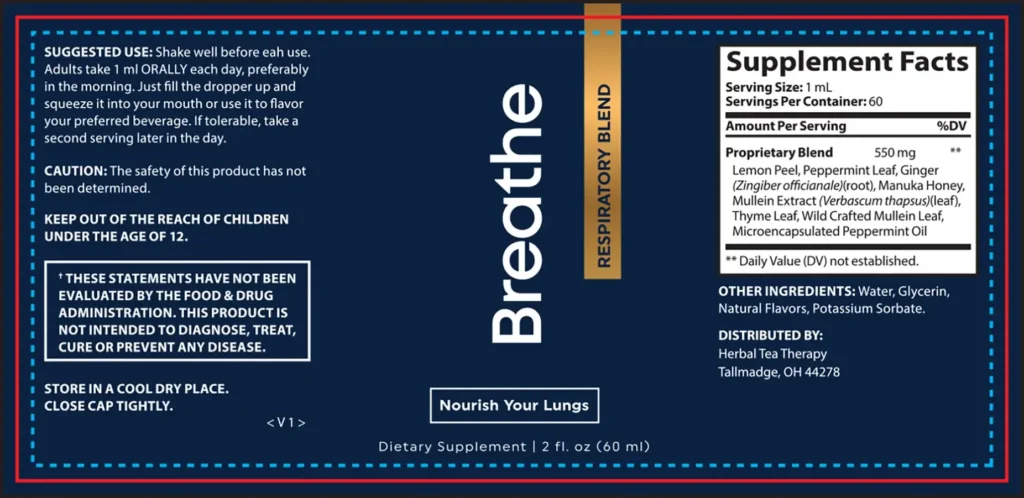

Developed and endorsed by respiratory health specialist Dr. Elizabeth Moffett, Breathe™ is a 100% natural breathing treatment that clears stubborn phlegm, opens your airways, and makes breathing feel effortless again – without inhalers, nebulizers, or daily steam inhalations. For many people, it’s been a life-changing alternative that delivers real relief without having to depend on medical devices or time-consuming routines. You deserve to breathe freely again, and Breathe™ offers a safe, natural way to do it starting today.

Peppermint Oil

Opens airways and promotes clear breathing.

Mullein Leaf

Helps clear phlegm and supports respiratory comfort.

- Natural Formula

- No Stimulants

- Non-GMO

- No Chemicals

- Easy-to-use liquid drops for fast absorption

FDA Compliance

All content and information found on this page are for informational purposes only and are not intended to diagnose, treat, cure or prevent any disease. The FDA hasn’t evaluated the statements provided on this page. Make sure you consult with a licensed doctor before taking any supplement or making any changes to your diet or exercise plan. Individual results may vary.